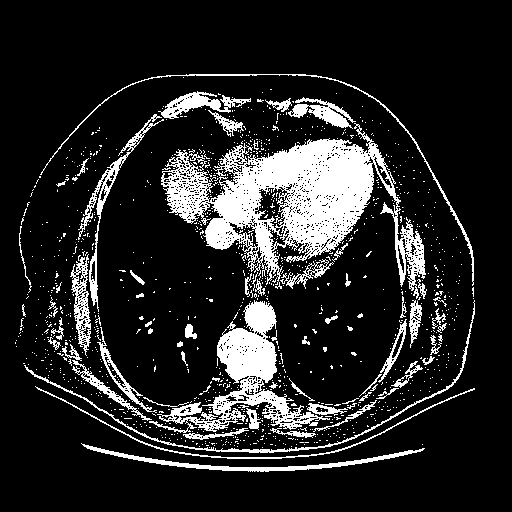

Generated VENOUS CT scan (A→B translation)

Full window (WL 1023.5, WW 4095 β†’ Low βˆ’1024, High +3071)

Actual HU range: [-1024.0, 3071.0]